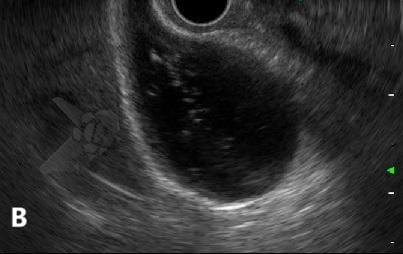

A poeira biliar foi definida como imagem flutuante hiperecogênica, sem sombra acústica posterior, observada ou acentuada após palpação abdominal³. Trata-se, portanto, da mesma entidade ecográfica que, no Brasil, vinha sendo tradicionalmente denominada “microlitíase”, mas que não se enquadra na definição do consenso internacional de microlitíase e acabou sendo praticamente ignorada pelo consenso — ou, em alguns casos, forçadamente incluída sob o amplo guarda-chuva do termo “barro biliar”.

A poeira biliar (“biliary dust”) foi definida como imagem flutuante hiperecogênica, sem sombra acústica posterior, observada ou acentuada após palpação abdominal — entidade ecográfica previamente denominada “microlitíase” ou “microcálculo” em nosso meio. A introdução desse termo visa conciliar os achados ecográficos frequentemente observados na prática diária com as definições estabelecidas pelo Consenso Internacional de 2023.